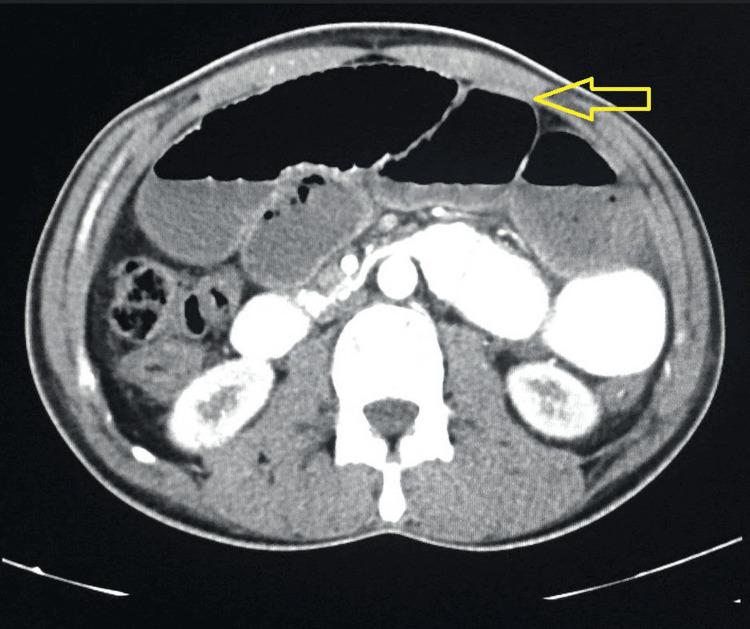

The defining feature across all six cases emerged during exploratory laparotomy, where a consistent finding stunned the surgical team: the discovery of a thick, fibrous membrane enveloping segments of the small bowel. The surgical procedure entailed meticulous dissection and subsequent removal of this membrane, with tissue samples dispatched for histopathological evaluation. This diagnostic approach conclusively confirmed the presence of abdominal cocoon syndrome in each of these patients.

在所有六例病例中,决定性特征在剖腹探查术中显现,一个一致的发现令手术团队震惊:发现一层厚厚的纤维膜包裹着小肠的部分节段。手术过程包括细致的分离并随后移除该膜,组织样本被送去进行组织病理学评估。这种诊断方法最终证实了这些患者均患有腹茧症。